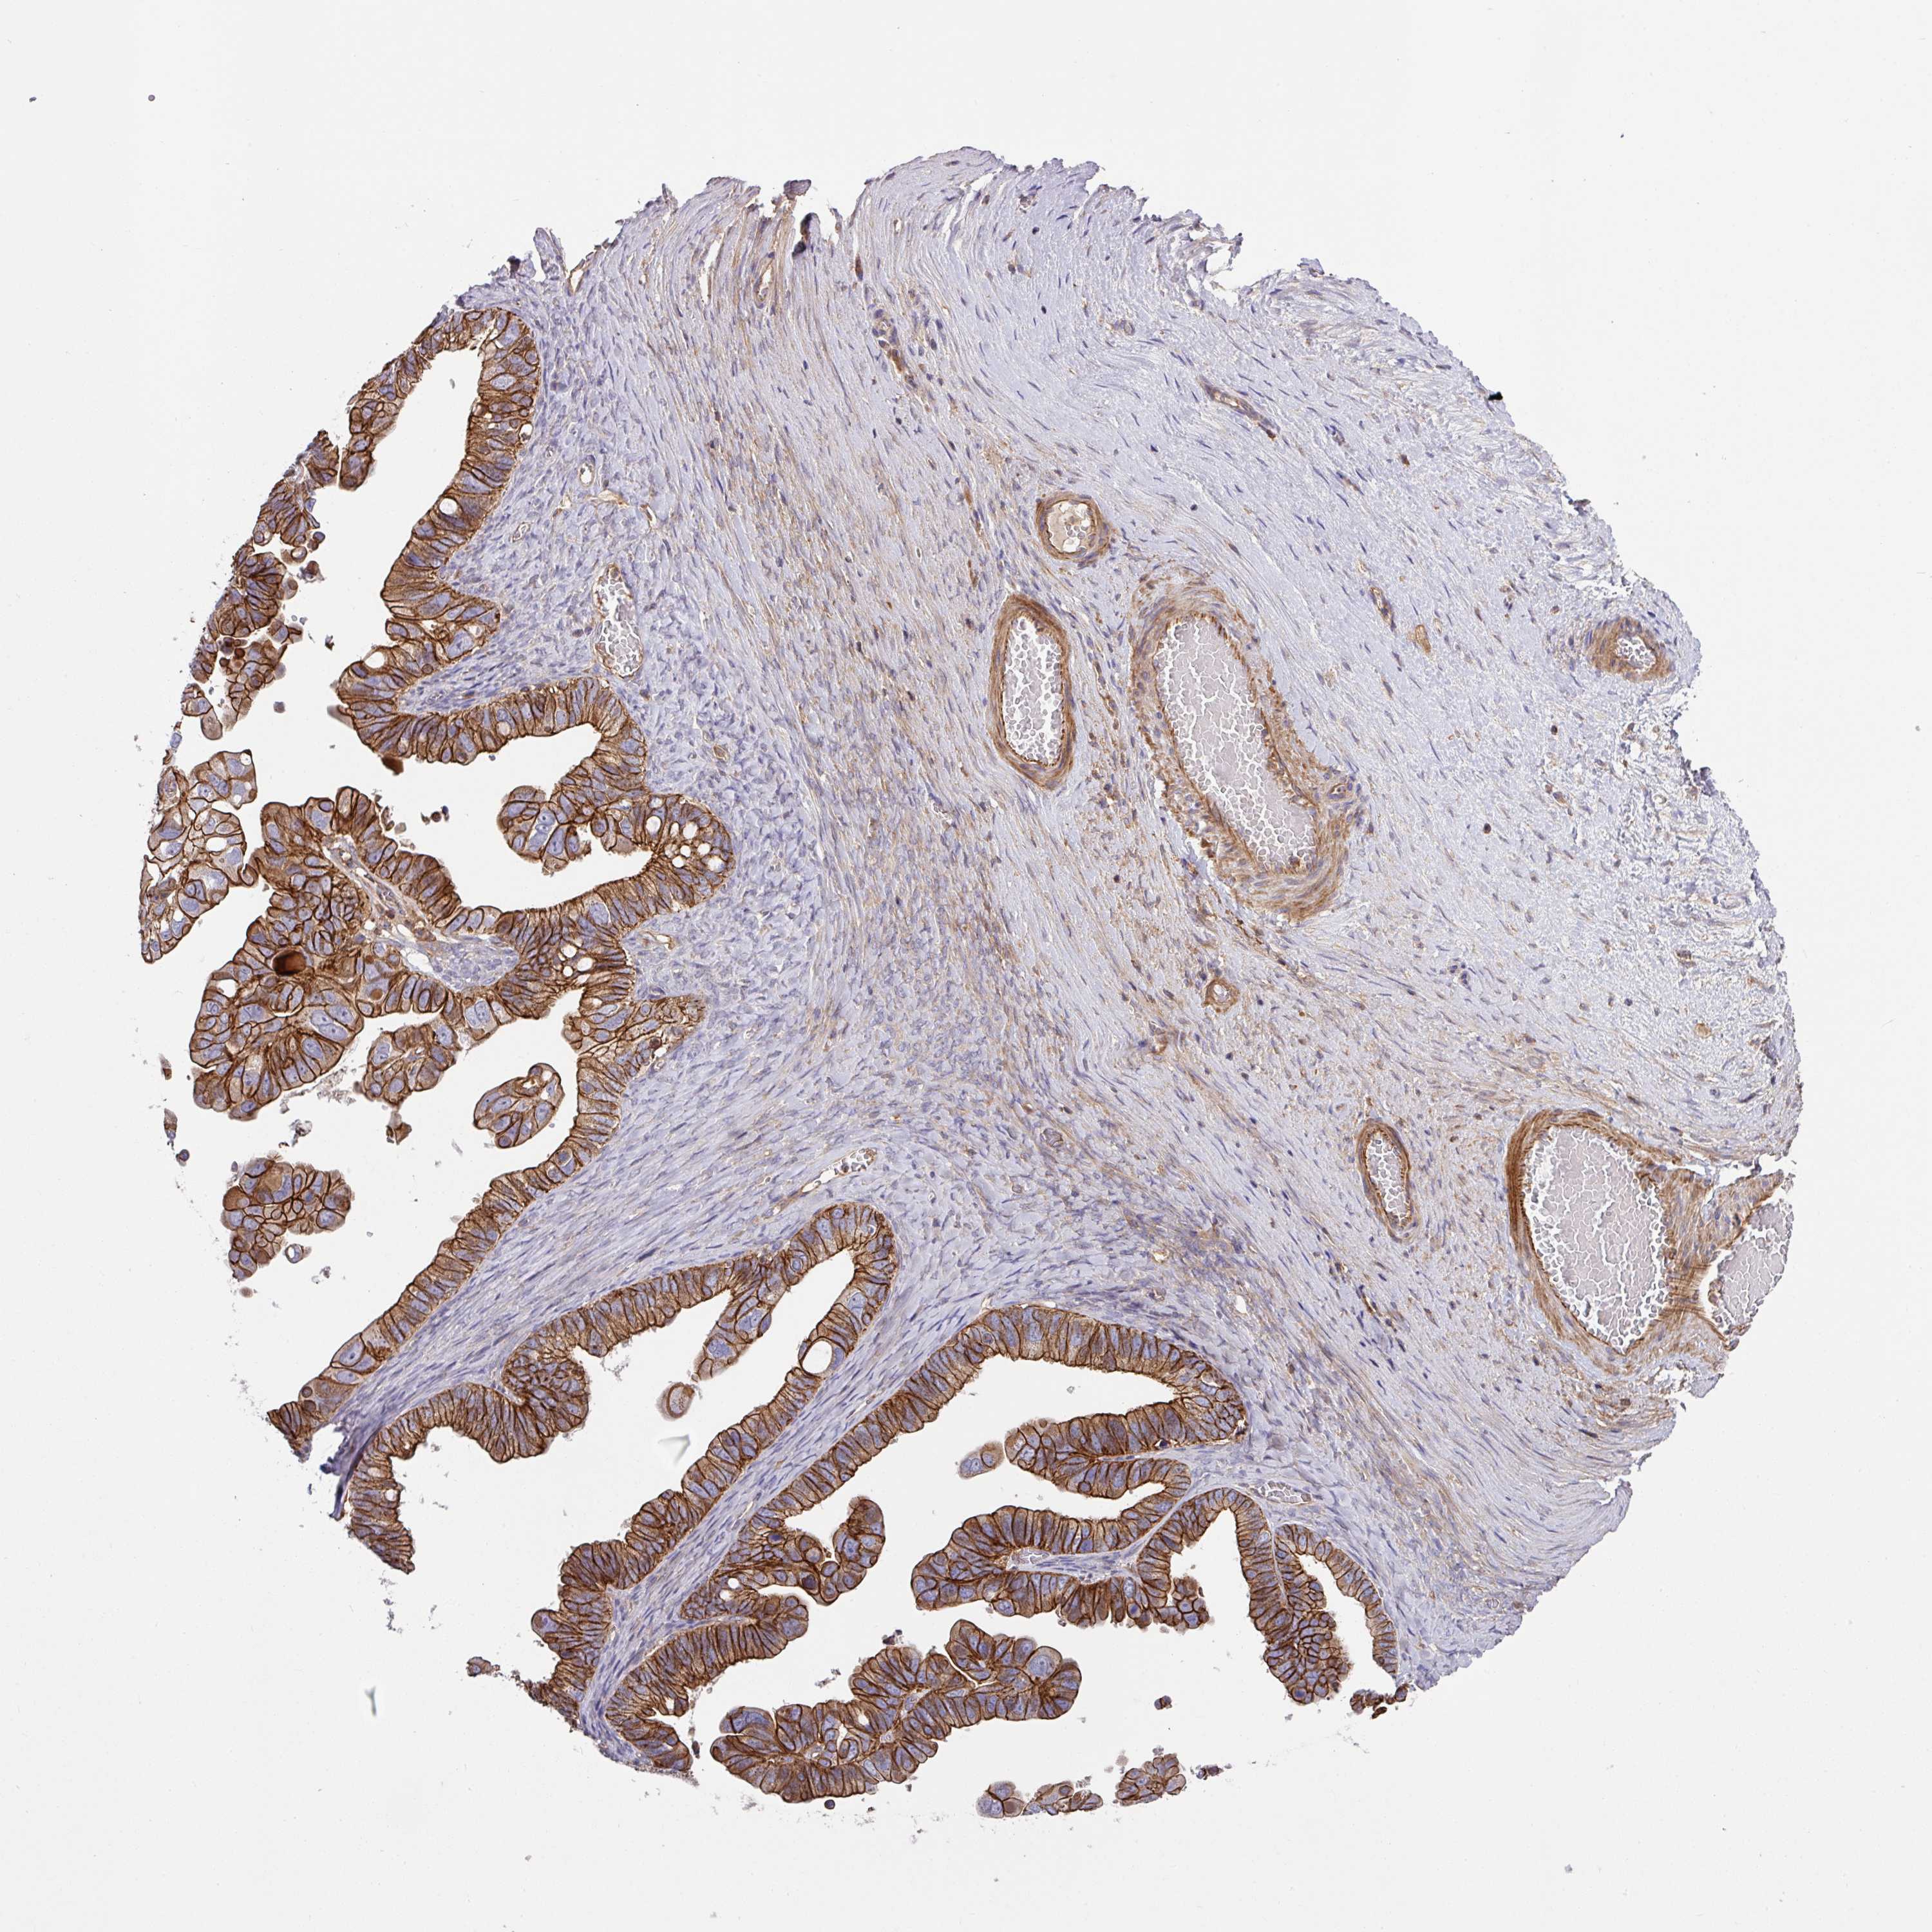

OVARIAN CANCER - Protein expressioni

A mouse-over function shows sample information and annotation data. Click on an image to view it in a full screen mode. Samples can be filtered based on level of antibody staining by selecting one or several of the following categories: high, medium, low and not detected. The assay and annotation is described here.

Note that samples used for immunohistochemistry by the Human Protein Atlas do not correspond to samples in the TCGA dataset.

Antibody stainingi

Antibody staining in the annotated cell types in the current human tissue is reported as not detected, low, medium, or high, based on conventional immunohistochemistry profiling in selected tissues. This score is based on the combination of the staining intensity and fraction of stained cells.

Each image is clickable and will lead to virtual microscopy that enables deeper exploration of all samples and also displays staining intensity scores, fraction scores and subcellular localization as well as patient and tissue information for each sample.

Antibody HPA051578

Staining

High

Medium

Low

Not detected

Intensity

Strong

Moderate

Weak

Negative

Quantity

>75%

75%-25%

<25%

None

Location

Nuclear

Cytoplasmic/membranous

Cytoplasmic/membranous,nuclear

Cystadenocarcinoma, serous, NOS

Carcinoma, NOS

Cystadenocarcinoma, mucinous, NOS

Carcinoma, endometroid